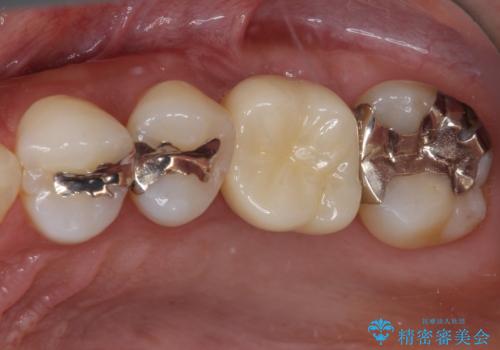

[入れ歯にしたくない] 臼歯部インプラント補綴